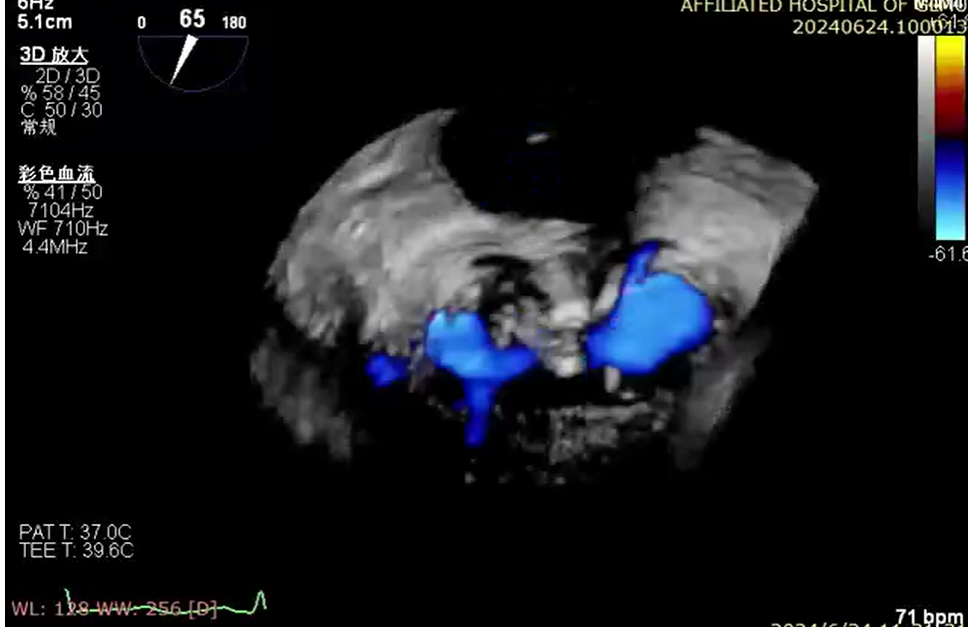

6 月 24 日,心血管内科一病区廖发荣、何武金团队在中山大学附属第一医院庄晓东教授的指导下,在患者右侧腹股沟区穿刺一个 3-5 毫米的小创口,然后将器械通过股静脉穿刺房间隔,把「二尖瓣夹系统」送入患者左心房,进而到达心脏的二尖瓣口,然后全程在食道三维超声引导下,精准夹合二尖瓣后瓣病变区域。

钳夹后,二尖瓣反流从术前 4+改善至 1+、夹合稳定、平均跨瓣压差 2 mmHg,患者术后心功能得到明显改善,无相关并发症,于 6 月 29 日顺利出院。7 月 12 日,患者到医院复查各项生理指标基本正常。